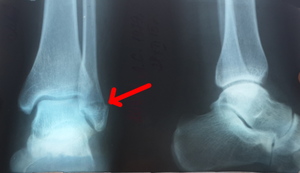

Врачи отмечают, что перелом лодыжки со смещением часто сопровождается резкой болью, отеком и ограничением подвижности в области голеностопного сустава. Пациенты могут испытывать трудности при попытке встать на ногу, а также замечают деформацию в области лодыжки. Важно своевременно обратиться за медицинской помощью, так как неправильное лечение может привести к долгосрочным последствиям.

Симптомы и признаки перелома лодыжки

При переломах щиколотки можно наблюдать следующие признаки:

- Кровоизлияния. В области повреждения образуется синяк, который может спуститься вниз к пятке. Этот симптом особенно заметен при переломах со смещением, так как в таких случаях происходит значительное повреждение кровеносных сосудов и мягких тканей.

- Изменение положения стопы. В зависимости от типа перелома стопа пострадавшего может поворачиваться наружу или внутрь. Этот признак характерен для серьёзных травм щиколотки — переломов, сопровождающихся вывихами.

Перелом внутренней лодыжки со смещением

Данная травма связана с повреждением большеберцовой кости. Внутренний перелом может быть как прямым, так и косым. Прямой перелом характеризуется пронацией и сопровождается растяжением дельтовидной связки, а также наружным поворотом стопы. Косой перелом может быть как открытым, так и закрытым. При этом типе травмы наблюдается супинация стопы, и происходит откалывание части внутренней лодыжки над пяточной костью.